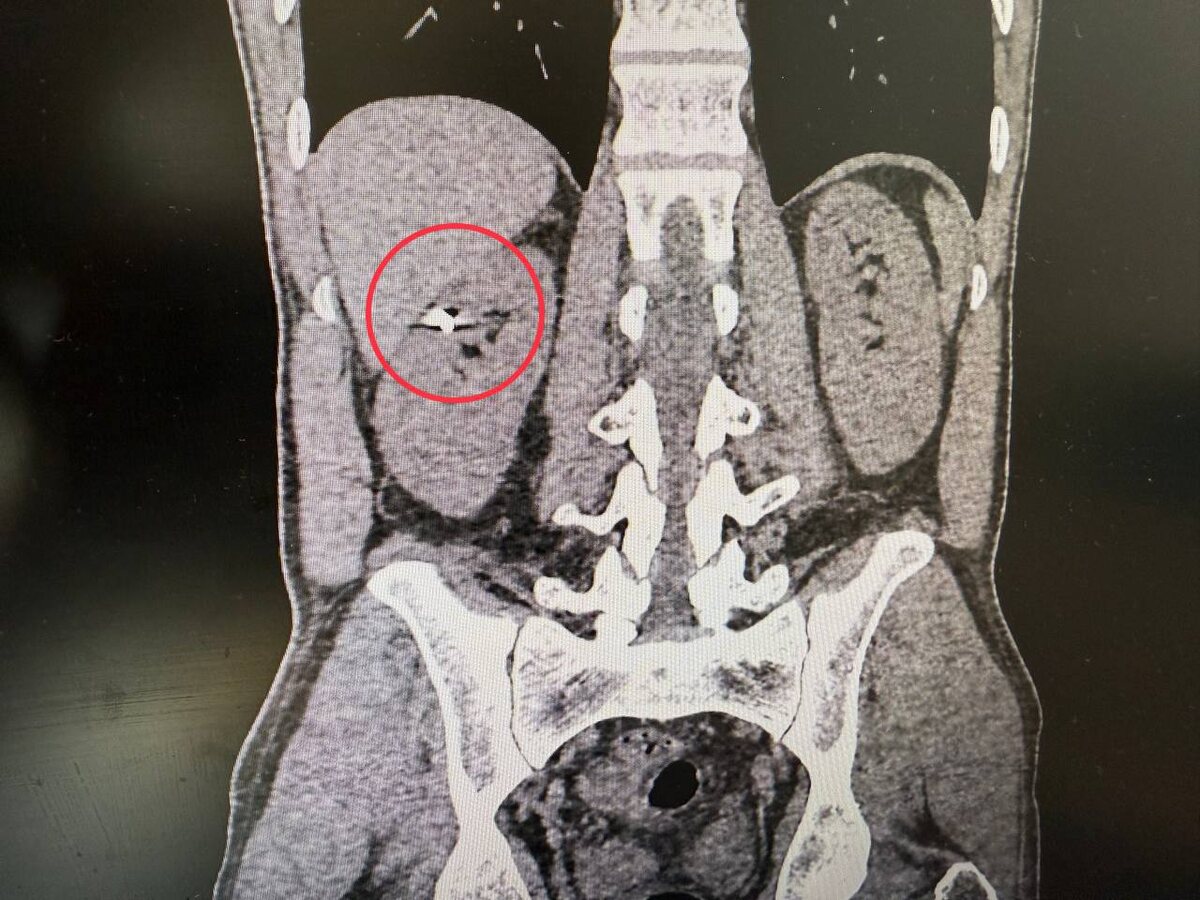

💬«По данным компьютерной томографии мы зафиксировали осколок в верхнем полюсе правой почки. Печень была тесно припаяна к почке, и извлечение осколка могло привести к серьезному кровотечению и потере органа. Мы сделали резекцию почки, причем лапароскопическим методом и извлекли осколок. Операция длилась около двух часов и прошла успешно. Главное – у нас получилось сохранить орган», - подчеркнул заведующий урологическим отделением Селим Везирханов

👍Пациента выписали на амбулаторное наблюдение на шестые сутки с хорошим самочувствием. Сохраненная почка по данным КТ с контрастированием к моменту выписки функционировала хорошо.

осколок в почке